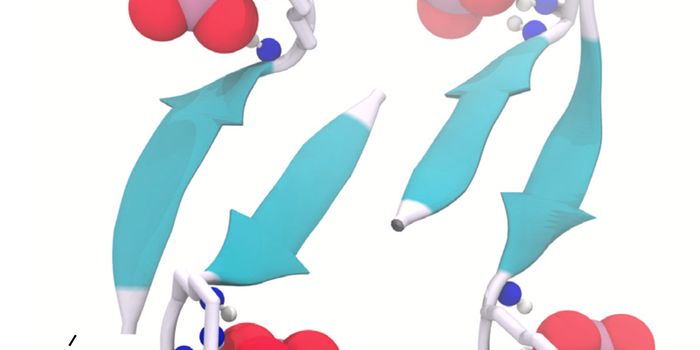

MAY 29, 2016Cell & Molecular BiologyThe amyloid-β peptide (Aβ) is a crucial protein in the development of Alzheimer’s disease (AD). Thought ...